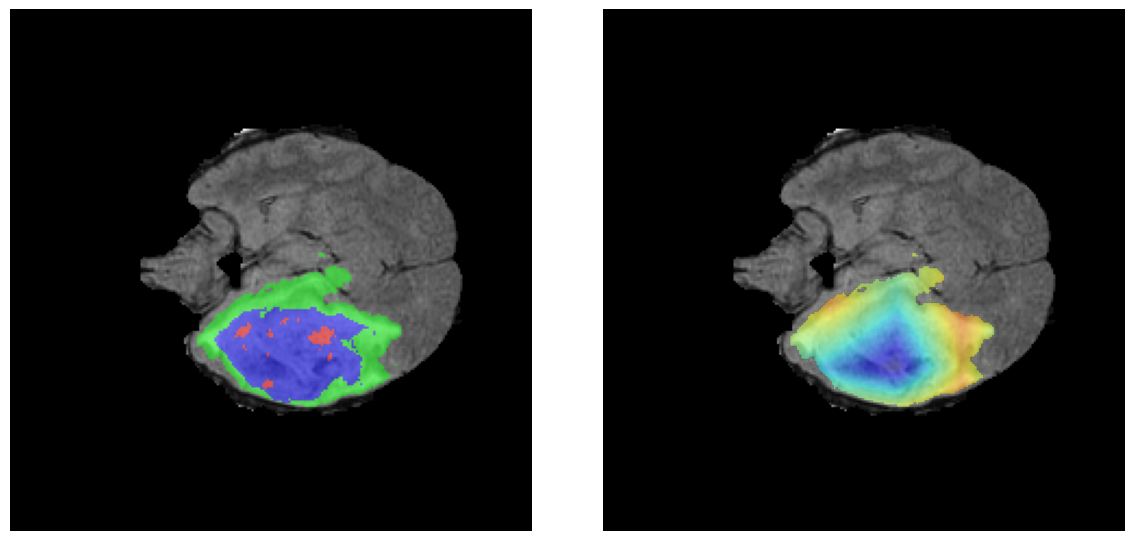

Ejemplos HGG - Atención en Núcleo Necrótico y Tumor Realzado

HGG Grad-CAM++ 1 HGG Grad-CAM++ 2 HGG Grad-CAM++ 3 HGG Grad-CAM++ 4 HGG Grad-CAM++ 5 HGG Grad-CAM++ 6

Los heatmaps muestran que el modelo concentra su atención en las regiones de Tumor Realzado (rojo) y Núcleo Necrótico (azul), características patológicas clave de los gliomas de alto grado.